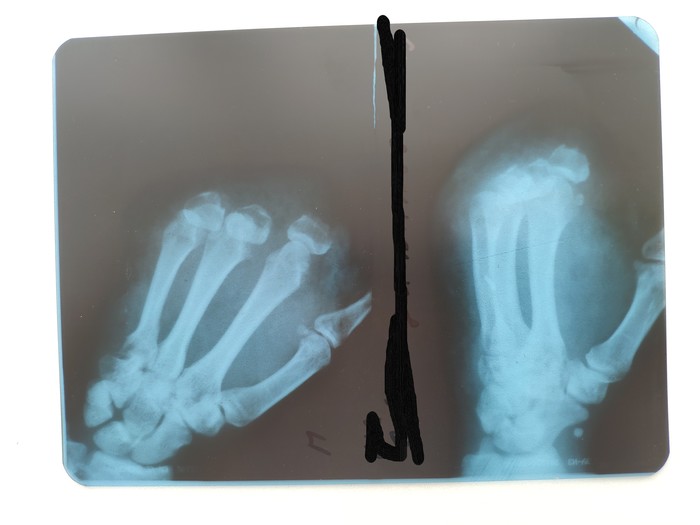

оказывается кости так интересно выглядят. это я сказал прибывшему врачу. у меня был шок. оторвало первые фаланги четырех пальцев и содрало кожу. не пострадал только большой палец.

повезли меня в районную больницу (не по месту жительства, т.к. работа находится в другом районе). там врачи осмотрели. сделали рентген-снимок

по снимку всё видно.

сделали ещё один снимок, где ещё более понятнее